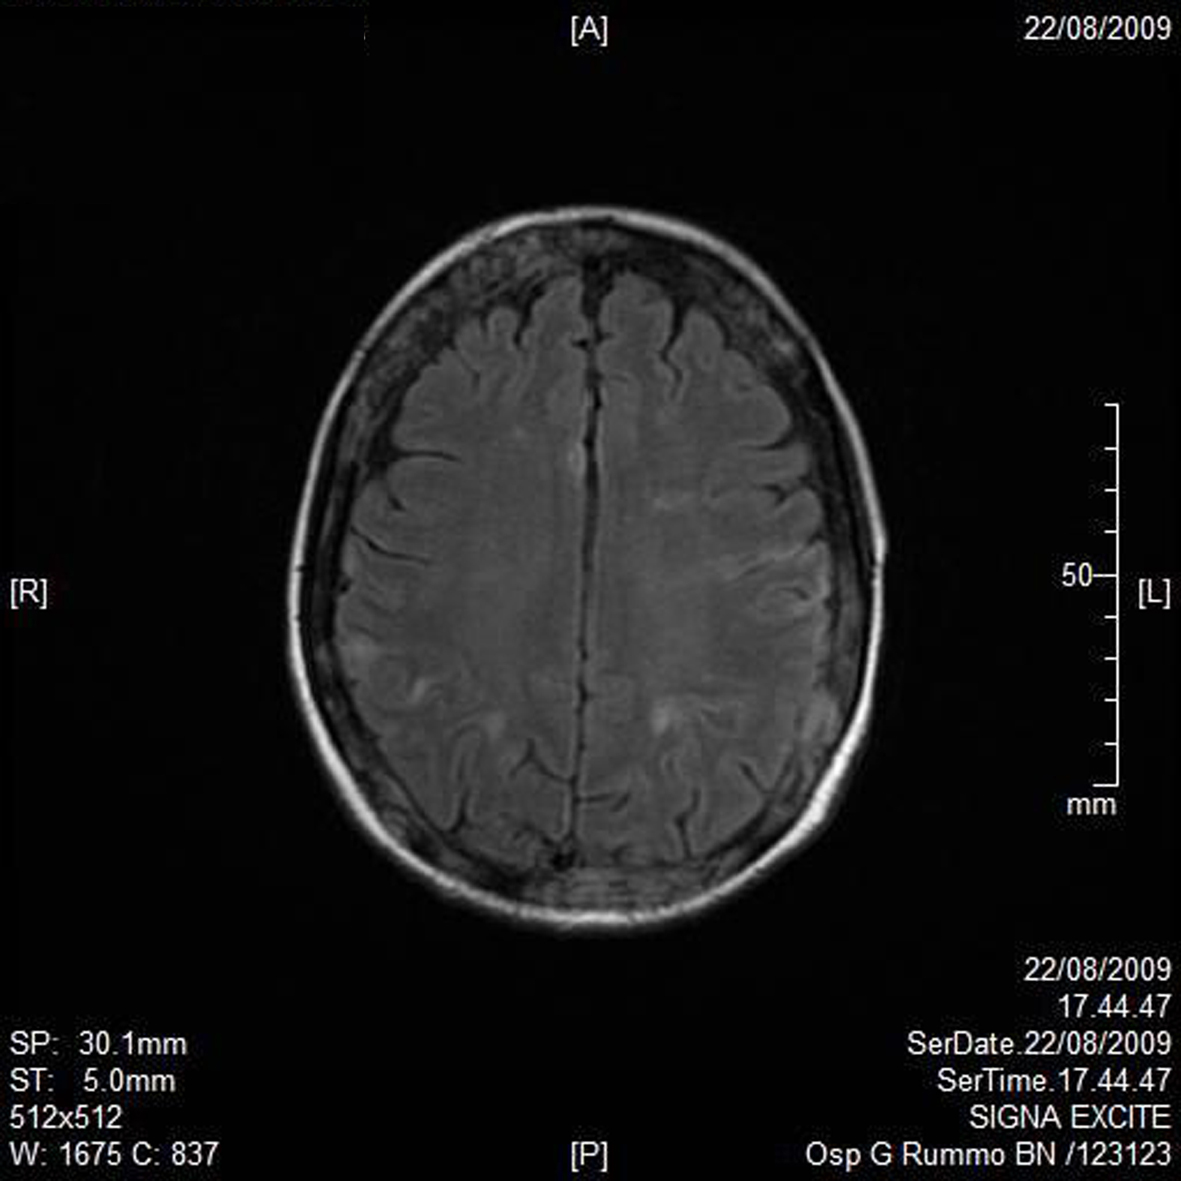

A RMN of the brain showed this clinical imaging (Fig. 1, 2) as a multinfartual area due to microembolization in blood vessels of the brain. The patient died after 10 days.

![]() Click for large image | Figure 1. Axial T1 imaging. |